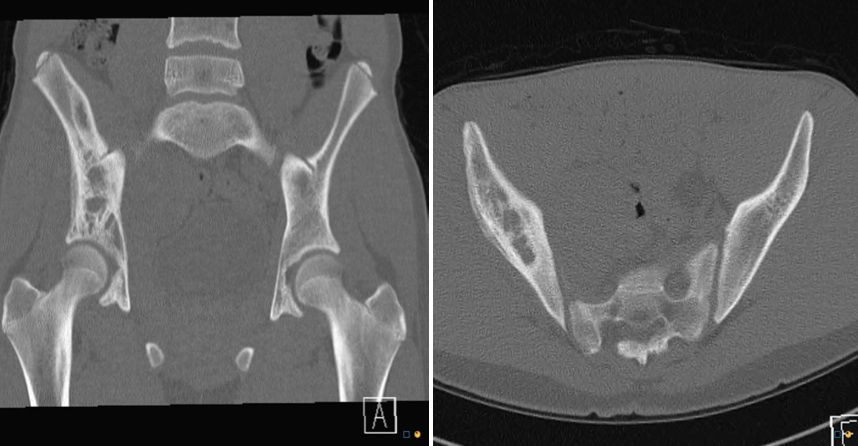

Figure 1 for case Ewing Sarcoma

Figure 1

Figure 2 for case Ewing Sarcoma

Figure 2